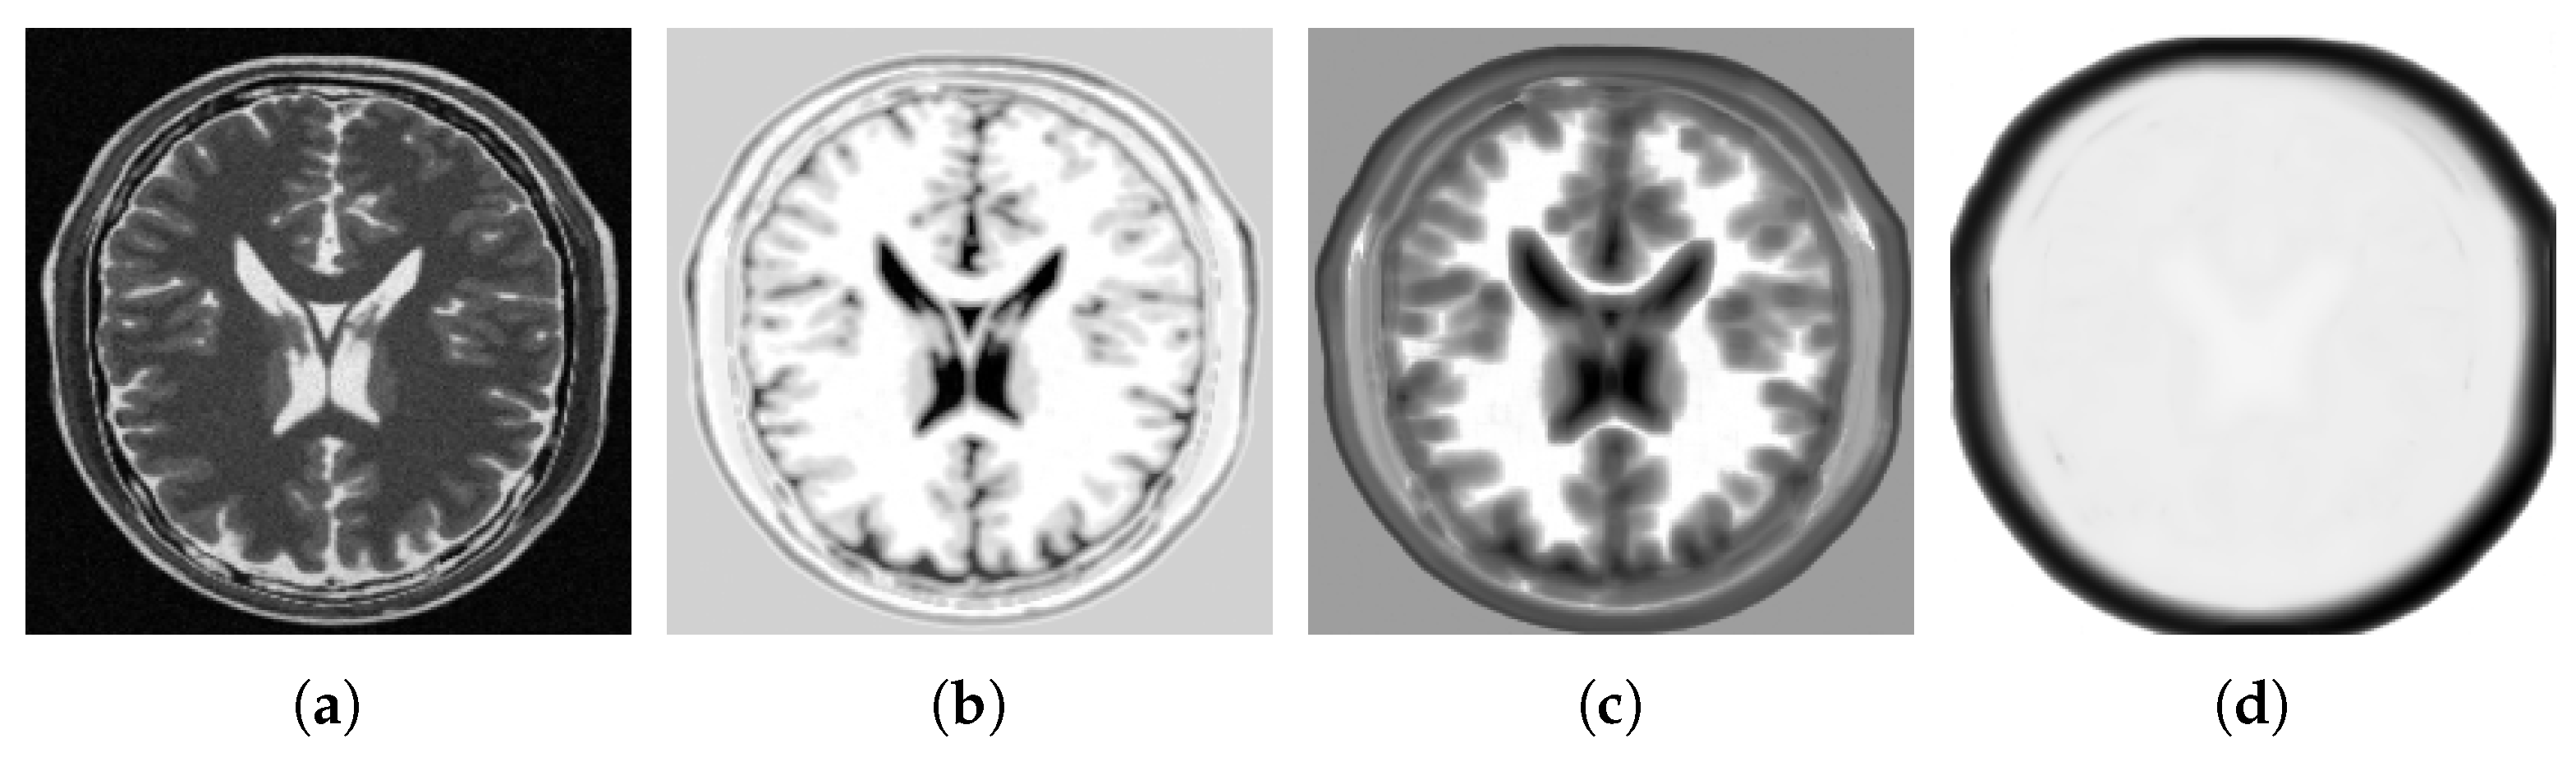

- Wachinger, C.; Navab, N. Entropy and Laplacian images: Structural representations for multi-modal registration. Med. Image Anal. 2012, 16, 1–17. [Google Scholar] [CrossRef] [PubMed]